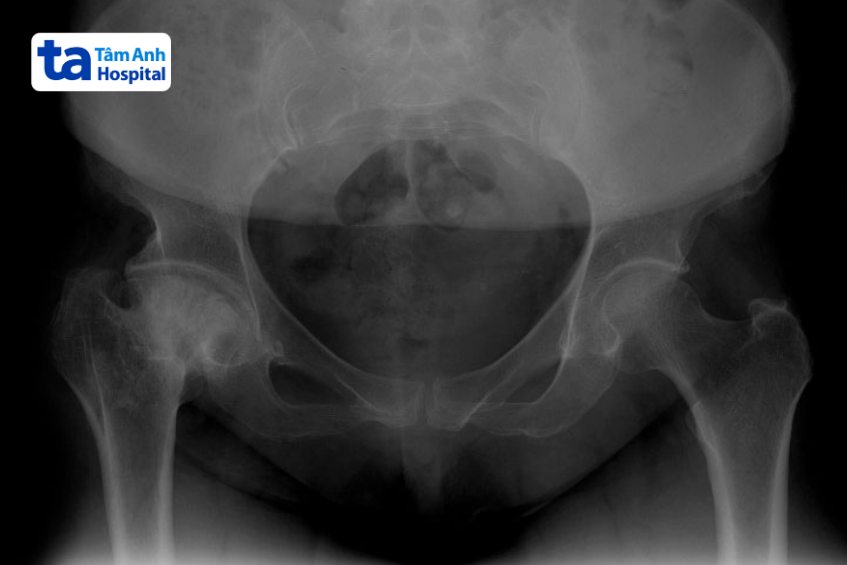

Hình ảnh viêm khớp háng trên X-quang có thể giúp bác sĩ đánh giá tình trạng và giai đoạn tiến triển của bệnh. Viêm khớp háng bao gồm 4 cấp độ tiến triển dựa vào mức độ tổn thương ở khớp háng: (1)

Chụp X-quang có thể được xem là phương pháp chẩn đoán hình ảnh viêm khớp háng đơn giản nhất và có chi phí rẻ nhất. Thông qua kết quả chụp phim X-quang, bác sĩ có thể quan sát được cấu trúc xương và tình trạng chấn thương ở các mô mềm xung quanh (nếu có). Trên phim X-quang không thể thấy được tình trạng sụn khớp, nhưng bác sĩ có thể chẩn đoán viêm khớp háng gián tiếp thông qua khoảng cách giữa xương đùi và ổ cối xương chậu.